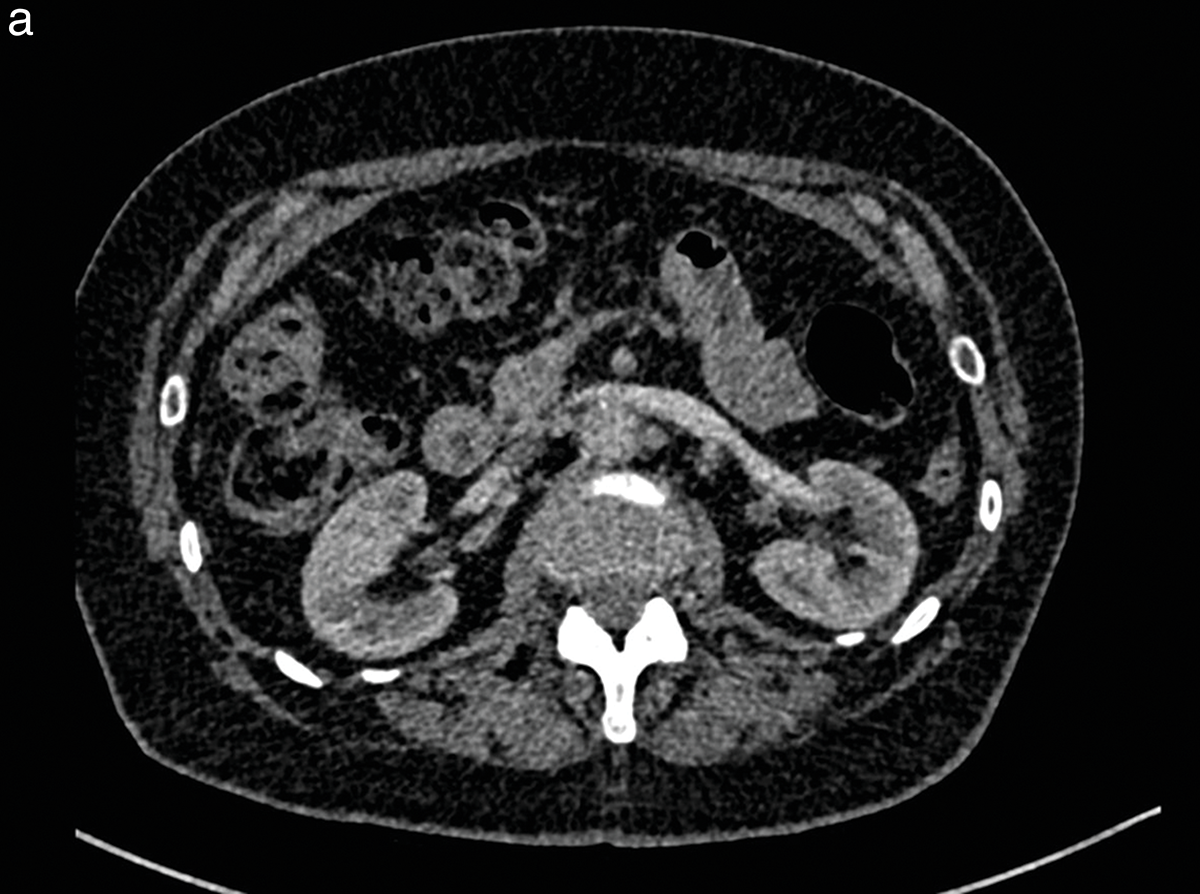

Figure 2 (a, b)

Patient with an abdominal aortic aneurysm, included in study Group 2.

After intravenous injection of 15 cc of iodinated contrast medium, the qualitative imaging score was 2 by the two independent observers for the axial slice at the renal artery level (a) and was 3 at the infrarenal level (b).